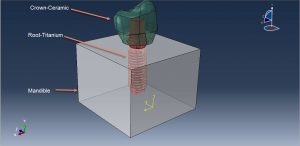

In this tutorial, Simulation dental implant in interaction with mandible bone under dynamic load in Abaqus has been investigated. The crown, Abutment, and mandible bone are modeled as three-dimensional parts. Dental implants are metal posts or frames that are surgically positioned into the jawbone beneath your gums. Once in place, they allow your dentist to mount replacement teeth onto them. Because implants fuse to your jawbone, they provide stable support for artificial teeth. Dentures and bridges mounted to implants won’t slip or shift in your mouth — an especially important benefit when eating and speaking. This secure fit helps the dentures and bridges — as well as individual crowns placed over implants — feel more natural than conventional bridges or dentures. You can see dome figures of the real and assembled parts below

The ceramic material with elastic-plastic behavior and ductile damage criterion is used for the crown. The titanium material with elastic-plastic material and Johnson-Cook damage are used to model root or abutment material. The mandible bone is modeled as an elestic-plastic material. The dynamic explicit procedure is appropriate for the dynamic loading conditions. The general contact algorithm with contact property is used to model all contact among the parts. The proper boundary condition is assigned to the mandible and concentrated force with smooth amplitude is selected for the crown. The mesh should be fine, because of the complexity of the model

During the analysis, the force causes the stress in the assembled parts and the critical zone can be extracted from the model. You can see some figures for the results below